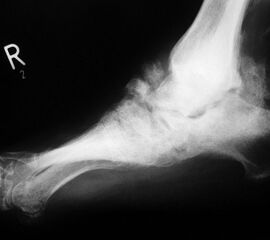

Abbildung 4

DNOAP Typ III (Abb. 4)

Betroffen sind hier das Chopart-Gelenk, also das Talonaviculargelenk und das Calcaneocuboidgekenk. Ein Beteiligung des Naviculocuneiformgelenks ist möglich. Das Längsgewölbe bricht zusammen und es entsteht der klassische diabetische Schaukelfuß – die Kombination aus einer reduzierten Inklination des Kalkaneus in Verbindung mit einer distalen Hackenfußstellung. Nach plantar prominente Knochenkanten und -fragmente können hier ebenfalls zu Ulzerationen der Fußsohle führen.